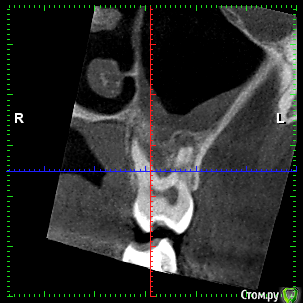

rezo47 Опубликовано 24 сентября, 2015 Автор Поделиться Опубликовано 24 сентября, 2015 Только пришло КТ, вопросов стало больше((( Ссылка на комментарий

kriokov Опубликовано 24 сентября, 2015 Поделиться Опубликовано 24 сентября, 2015 27 удаляйте Ссылка на комментарий

rezo47 Опубликовано 24 сентября, 2015 Автор Поделиться Опубликовано 24 сентября, 2015 (изменено) 27 удаляйтеДиагноз? Изменено 24 сентября, 2015 пользователем rezo47 Ссылка на комментарий

kladoffka Опубликовано 24 сентября, 2015 Поделиться Опубликовано 24 сентября, 2015 Хр пр 2 Ссылка на комментарий

kriokov Опубликовано 24 сентября, 2015 Поделиться Опубликовано 24 сентября, 2015 Диагноз?что хотите, на выбор(например- "не жилец" ) Ссылка на комментарий

red_butler Опубликовано 24 сентября, 2015 Поделиться Опубликовано 24 сентября, 2015 сначала гистология, потом лечение Ссылка на комментарий